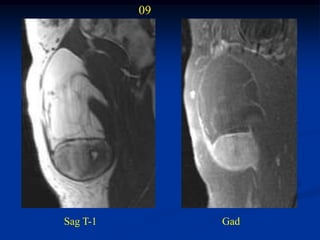

Case #1198.3            CT scan 4/06

09

Sag T-1        Gad

Axial T-1 upper   T-2 upper

T-2 lower         Cor STIR